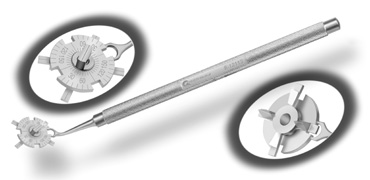

disruption, but may mask an unintentional perforation. The extent of arc to be incised may be demarcated in several different

ways. Our preferred method makes use of a modified Fine-Thornton fixation

ring (Nichamin Fixation Ring and Gauge; Mastel Precision, Storz, Rhein

Medical). This instrument serves to fixate and position

the globe in order to optimize incision placement, as well as to delineate

the extent of arc to be incised. One visually extrapolates from

the limbus to marks on the surface of the ring. Each incremental mark

is 10 degrees apart, and bold hash marks (180 degrees) opposite

to each other serve to align and center the incision over the steep

meridian. This approach obviates the need to ink and physically mark

the cornea. If one desires, particularly when first gaining experience

with LRIs, a two-cut RK marker may be used to place ink marks upon the

cornea to show the exact extent of arc that is to be incised, in conjunction

with the fixation ring/gauge (Fig. 4). Alternatively, various press-on markers are available, such as

those made by Rhein Medical (Dell-Nichamin Marker, Nichamin-Kershner

Marker, or the Ruminson Marker) (Fig. 5). ASICO and other instrument companies offer a full line of dedicated

markers, rings, and blades for performing LRIs.  Fig. 4. The Nichamin Fixation Ring and Gauge serves to both fixate the globe and

delineate the extent of arc to be incised; a two-cut radial marker may

be used to mark the extent of arc to be incised, and the Mastel Nichamin

Force AK Diamond Blade with preset depth of 600 microns. Fig. 4. The Nichamin Fixation Ring and Gauge serves to both fixate the globe and

delineate the extent of arc to be incised; a two-cut radial marker may

be used to mark the extent of arc to be incised, and the Mastel Nichamin

Force AK Diamond Blade with preset depth of 600 microns.